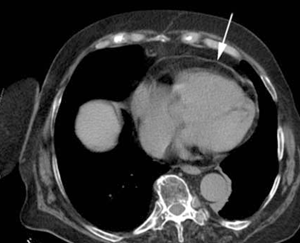

Se solicitó ecocardiografía transtorácica que mostró: fracción de eyección del ventrículo izquierdo (FEVI) 55%, ventrículo izquierdo con hipertrofia leve, hipoquinesia biventricular difusa, dilatación leve de aorta ascendente, aurícula izquierda moderadamente dilatada, engrosamiento pericárdico con probable derrame y colapso parcial de la aurícula derecha. Se solicitó tomografía de tórax (TC) sin contraste (figuras 1 y 2) que mostró una imagen típica de lipoma pericárdico, de 48 por 33 mm, que provocaba colapso de la aurícula derecha, considerándose la causa del taponamiento a baja presión. La angiografía coronaria no evidenció lesiones estenóticas significativas.

Figura 2: Tomografía de tórax sin contraste que muestra derrame pericárdico leve.